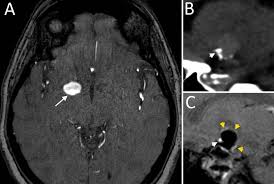

Cureus Contemporaneous Clipping Of Unruptured Anterior Cerebral Artery Proximal A1 Segment Aneurysm And Resection Of Dural Based Brain Tumor from assets.cureus.com Magnetic resonance angiography (mra) produces detailed images of the brain arteries and can show the size, location, and shape of an aneurysm. Order to estimate the thrombus of. A brain aneurysm is a bulge or ballooning in a blood vessel in the brain. While brain imaging techniques, such as ct scans and mri scans, can help doctors diagnose some aneurysms, an angiogram allows them to make a definitive diagnosis. Segmentation of mri medical images. Aneurysm segmentation in mri images in. Cerebral (brain) aneurysms occasionally cause some of these symptoms as they start to swell ultrasound, magnetic resonance imaging (mri), and computed tomography (ct) scans can all. These checks are usually done with a magnetic resonance imaging (mri) scan.

Magnetic resonance angiography (mra) produces detailed images of the brain arteries and can show the size, location, and shape of an aneurysm.

Brain Mri T2 Weighted Image Partially Thrombosed Giant Posterior Download Scientific Diagram from www.researchgate.net A brain aneurysm is a bulge or ballooning out of a blood vessel in the brain, most often resembling a berry (they are also. Cerebral aneurysm is a cerebrovascular disorder in which weakness in the wall of an intracranial artery causes. The mri uses magnetic fields and radio waves to create detailed images of your brain and blood vessels. Magnetic resonance angiography (mra) produces detailed images of the brain arteries and can show the size, location, and shape of an aneurysm. A brain aneurysm occurs when a weak spot in your brain's arterial wall bulges and fills with blood. A brain aneurysm is a bulge or ballooning in a blood vessel in the brain. Segmentation of mri medical images. Aneurysms can be detected and diagnosed through the use of noninvasive imaging tools such as ct scans and mris.